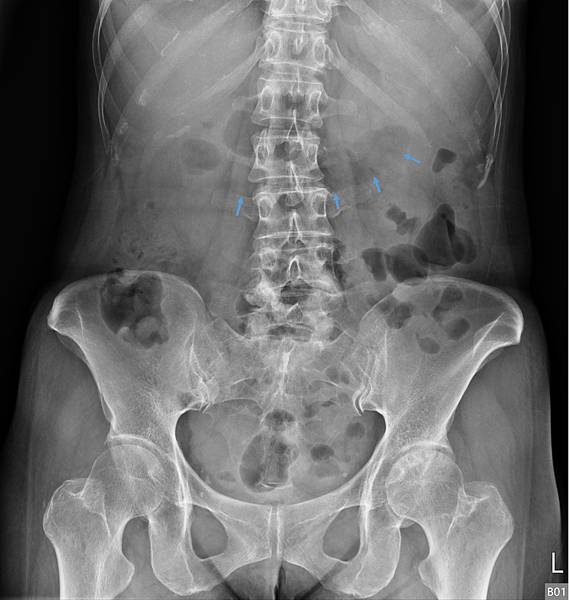

下面的病人,80歲女性,長期胃食道逆流,每半年做一次胃鏡(診斷GERD LA Gr A),斷斷續續吃PPI兩三年。GERD LA Gr A這種診斷是假的胃食道逆流,方便醫師開PPI而已。照一張X光片,真實的情況如下:

她的問題出在腸道產氣細菌製造出來的腸氣影響(抑制)大腸蠕動,大腸蠕動慢,吸收水分多,造成升結腸的糞便因水分吸收過多而呈羊屎狀。解決方式是「清腸+益生菌」,兩週後的X光片如下: